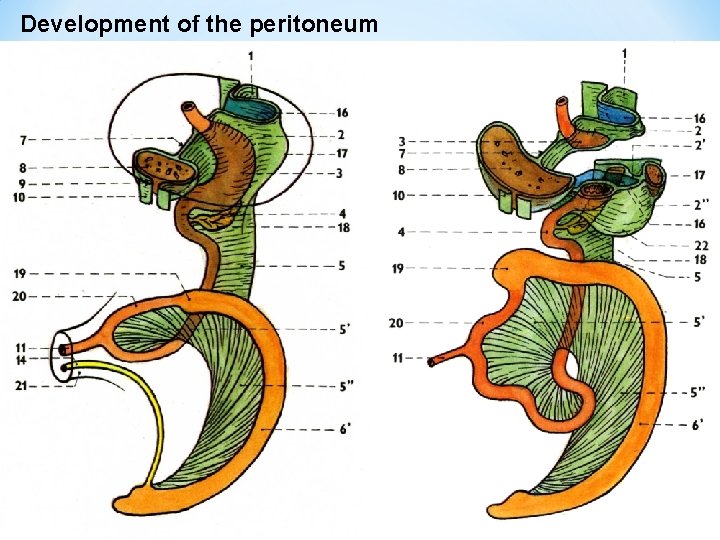

Development of the peritoneum